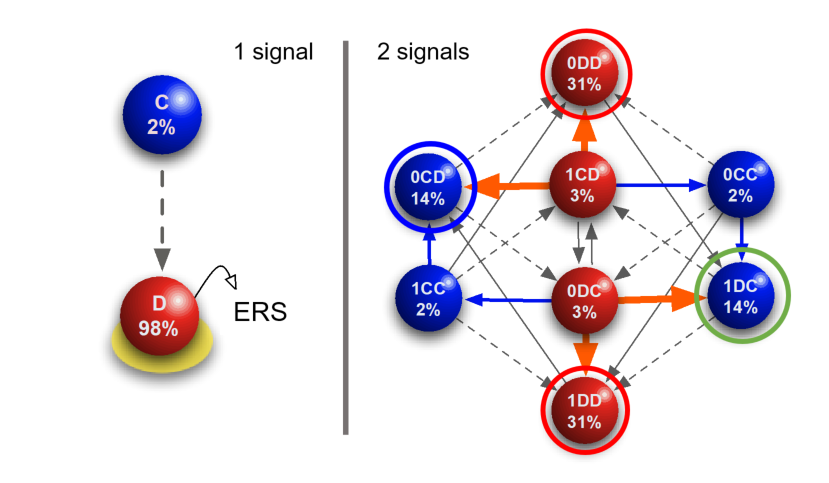

C. 221.

Multistage feedback-driven compartmental dynamics of hematopoiesis

Nathaniel Mon Père, Tom Lenaerts, Jorge M. Pacheco, David Dingli

iScience 24 (2021) 102326

C. 209.

Evolutionary dynamics of paroxysmal nocturnal hemoglobinuria

Nathaniel mon Père, Tom Lenaerts, Jorge M. Pacheco, David Dingli

PLoS Computational Biology 14,6 (2018) e1006133

C. 177.